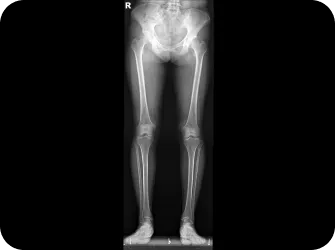

척추와 골반이 틀어지면 체중이 고르게 분산되지 않고 보행 패턴도 불균형해져서 한쪽 발에 과도한 부담이 집중됩니다. 여기에 척추 디스크나 협착증으로 인한 신경 압박은 발의 통증을 더욱 악화시키는데, 특히 노화로 엉덩이 근육이 약해지면서 통증이 가속화 되는 경우가 많습니다. 발 질환의 효과적인 치료를 위해서는 척추와 골반을 바로 잡아 양발에 체중이 균등하게 분산되도록 하는것이 중요합니다.

• 발목과 무릎, 고관절 정렬이 틀어지면서 다리가 휘었다.

다리 길이 엑스레이 검사